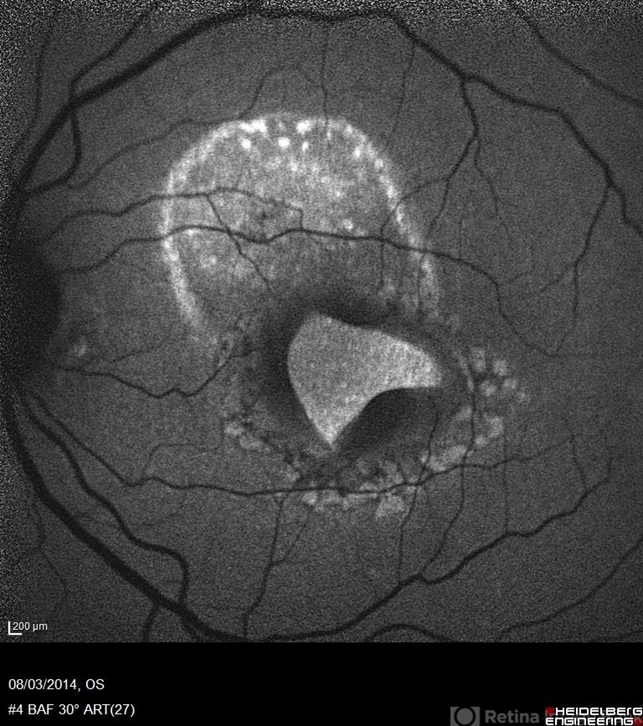

- autofluorescence imaging, macular hole

- Blue autofluorescence (BAF) a 40-year-old man with macular tear (had a photocoagulation laser).